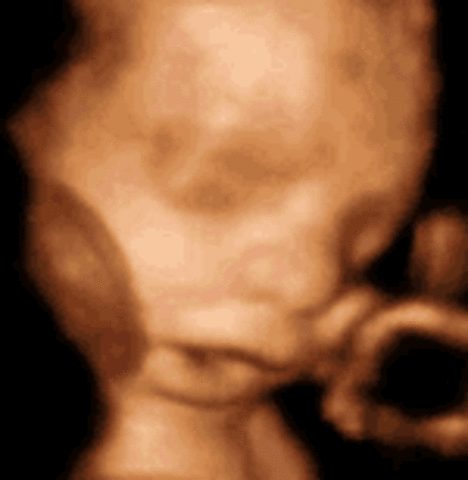

week 26

Baby's eyes beging to open. Coordination so the baby can suck on his thumb

• week 27

week 27

Looks are almost fully developed. Retina at the back of baby's eyes are starting to develop.